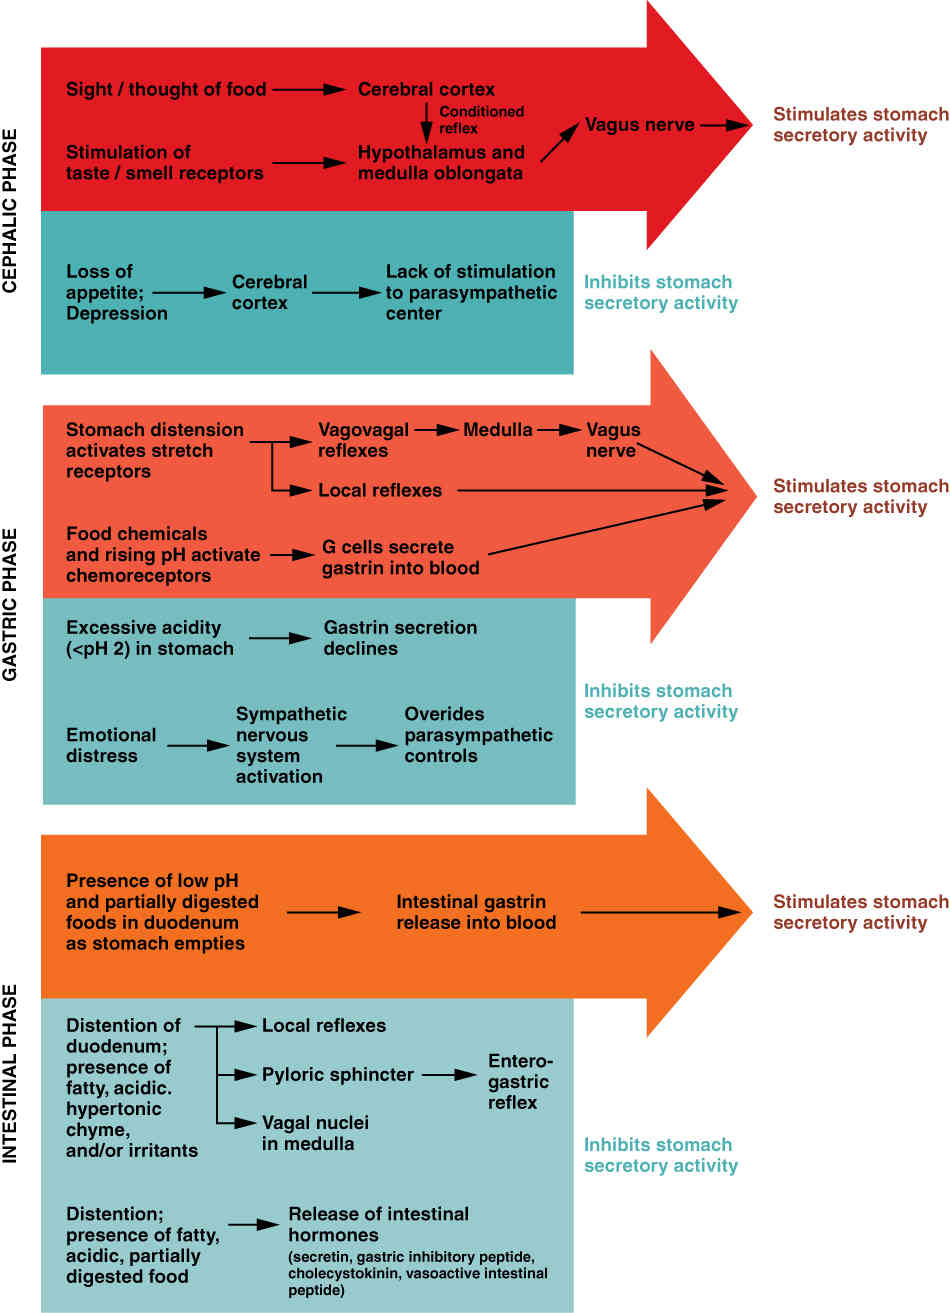

This page is under construction. For now, it is just a resource of the images found in the OpenStax Anatomy and Physiology Handbook. It wil slowly change into a revision tool. Each slide has a number. Use this to refer to the slide. When completed, it will have an unlabelled section, with labelled slides in parallel. On the unlabelled slides, write your answer and use the labelled slide to assess yourself. Keep track by also noting the number on each slide. Improvement at each attempt is important, more so than full marks on a first attempt.